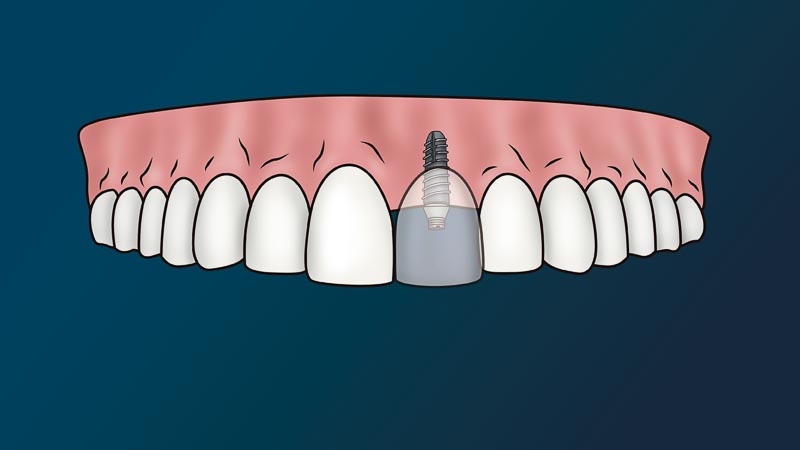

What is the Dental Implant Process in Mexico?

The dentist will attach to your jaw a metal root (implant) and place on top a fake tooth (crown). We call this procedure, a dental implant. Since this procedure is non-life threatening and non-essential to one’s immediate health, it considered a cosmetic procedure. In other words, medical or dental insurance policies don’t cover this procedure.